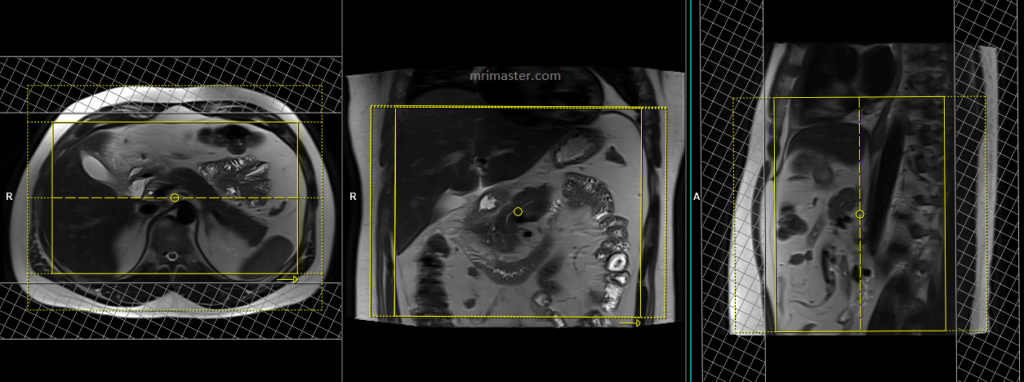

Small FOV T2 tse\HASTE breath hold 3mm

Plan the axial slices on the coronal breath-hold images and position the block horizontally across the abdomen as shown. Verify the positioning in the other two planes. Establish an appropriate angle in the sagittal plane, aligning it horizontally across the abdomen. The slices must be sufficient to cover the entire pancreas, starting one inch above the pancreatic tail and extending down to the C loop of the duodenum. The phase direction should be from right to left to minimize ghosting artifacts from the anterior abdominal wall. Use phase oversampling to prevent wrap-around artifacts. Consider adding saturation bands at the top and bottom of the block to minimize artifacts caused by fat signal, arterial pulsation, and breathing. Instruct the patient to hold their breath during image acquisition.

Note:Scans achieve better results when performed with a right-to-left phase direction and 70% oversampling. This choice is made to prevent artifacts caused by motion of the abdominal wall fat. However, in most scanners, implementing this option is not feasible due to the additional oversampling, which would extend the breath-hold time beyond what patients can manage. As a result, we conduct the scan with an anterior-posterior phase direction on our 1.5T scanner and right-to-left on our 3T scanner. If TSE images exhibit excessive artifacts, consider utilizing a HASTE sequence.